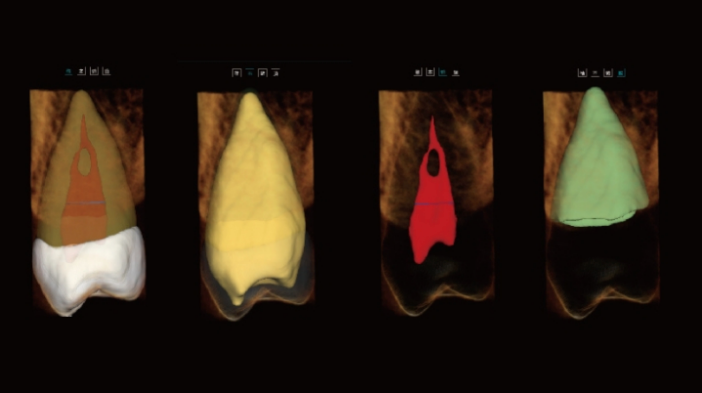

Tecnologia Inovadora Root-Bone Glass

Suporta o posicionamento manual dos dentes, a remoção dentária e a observação tridimensional da câmara pulpar.

Permite o planeamento imediato de extrações e implantes.

Análise Dentária 3D Abrangente: segmentação completa do dente com medições automáticas, planeamento do percurso de acesso e avaliação precisa de cáries.

Visualização Endodôntica Avançada: observação 3D de cáries interproximais, defeitos estruturais e morfologia dos canais radiculares, garantindo que nenhum canal passa despercebido.

Segmentação Completa da Estrutura Dentária: realce automático do esmalte, dentina, polpa e estruturas periodontais, permitindo a visualização das alterações morfológicas.

Mapeamento Avançado dos Canais Radiculares: visualização clara dos canais MB2 e em forma de C, apoiando um tratamento endodôntico preciso e minimizando o risco de canais não detetados.

Visualização Especial dos Canais Radiculares

vermite a visualização de morfologias especiais dos canais radiculares (MB2 e canais em forma de C), orientando os procedimentos endodônticos.

Ajuda a evitar a omissão de canais.